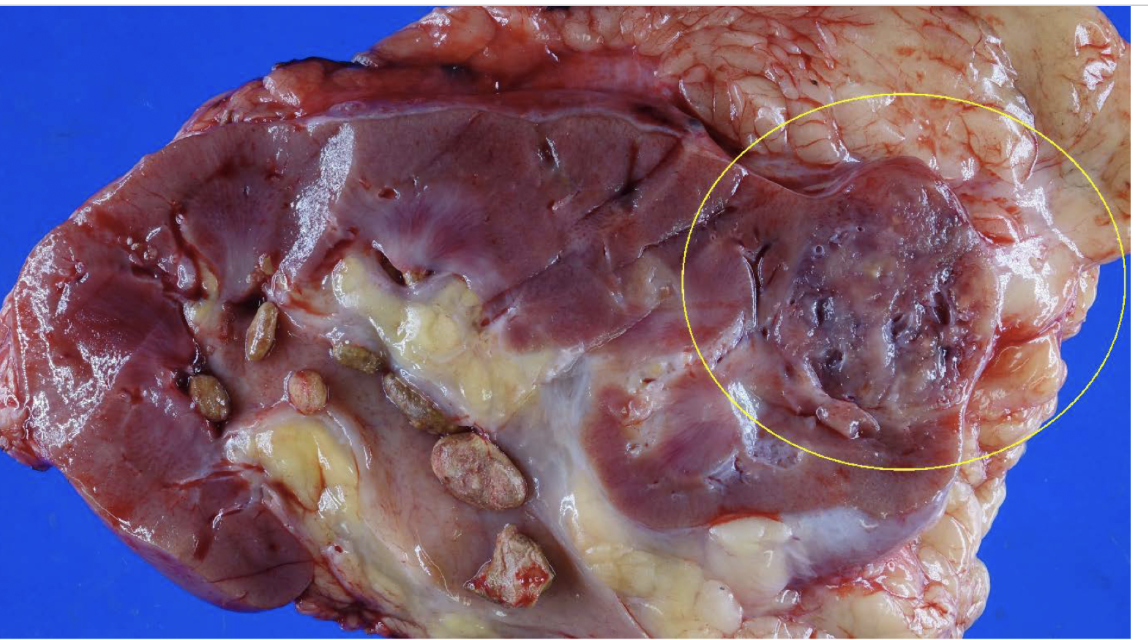

oncocytoma

arises from intercalated cells of CD

oncocytoma

numerous mitochondria = granular eosinophilic cytoplasm

oncocytoma

mahogany brown with central scar